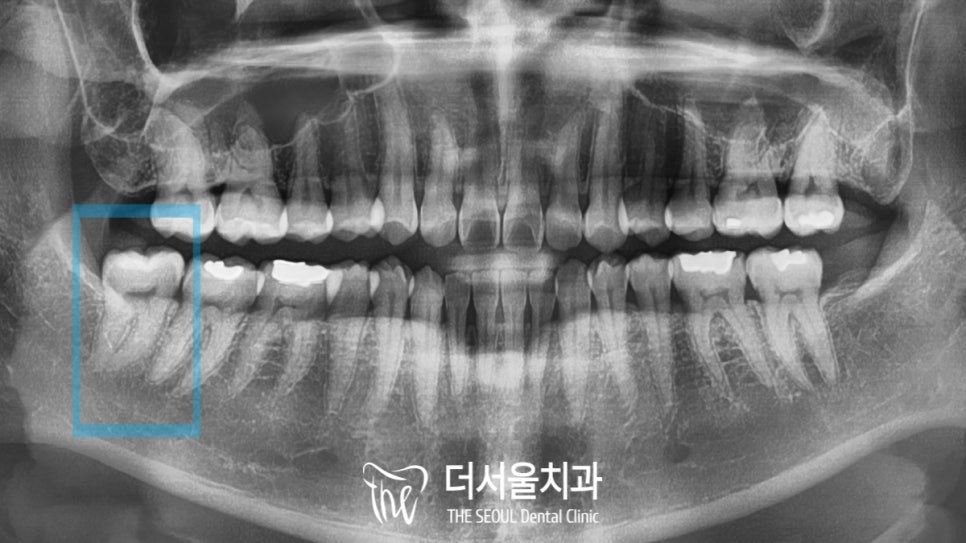

음 형태는 올곧게 자랐으나 관리가 잘되지 않아

치아 우식이 생겨버리고 말았네요.

파노라마 상에서는 신경관과 치아의 뿌리가

굉장히 근접해있는 것으로 확인되었습니다.